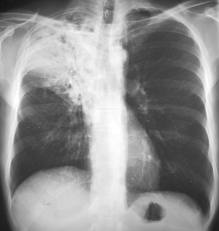

SANTO DOMINGO. Si usted tiene más de 15 días con tos y catarro, es posible que pueda padecer tuberculosis. Para descartarlo, es necesario que asista de inmediato al centro de salud más cercano.

Otro dato que debe tomar en cuenta es que esta enfermedad, producida por una bacteria, es curable. Pero también es importante que sepa que el tratamiento es gratuito, y ofrecido en la mayoría de centros de atención primaria y hospitales del país.